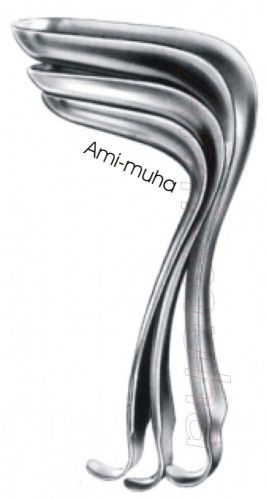

3 PCS SET Kristeller Vaginal Speculum

3 PCS SET PEDERSON VAGINAL SPECULUM